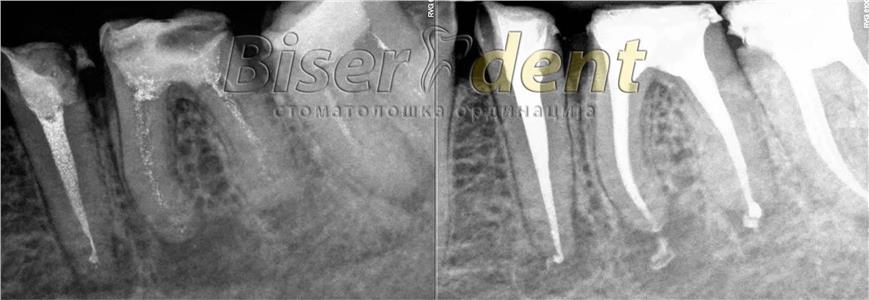

Современата ендодонција е целосно застапена во нашата ординација. Тоа вклучува примена на апекс локатор (за прецизно одредување на должината на коренските канали), системи за машинска обработка на истите (Protaper, Endo eze), системи за иригација (испирање) и дезинфекција на каналите, ласер за комплетна стерилизација, високо квалитено полнење и секако потврда на спроведениот ендодонтски третман со рентген снимка.